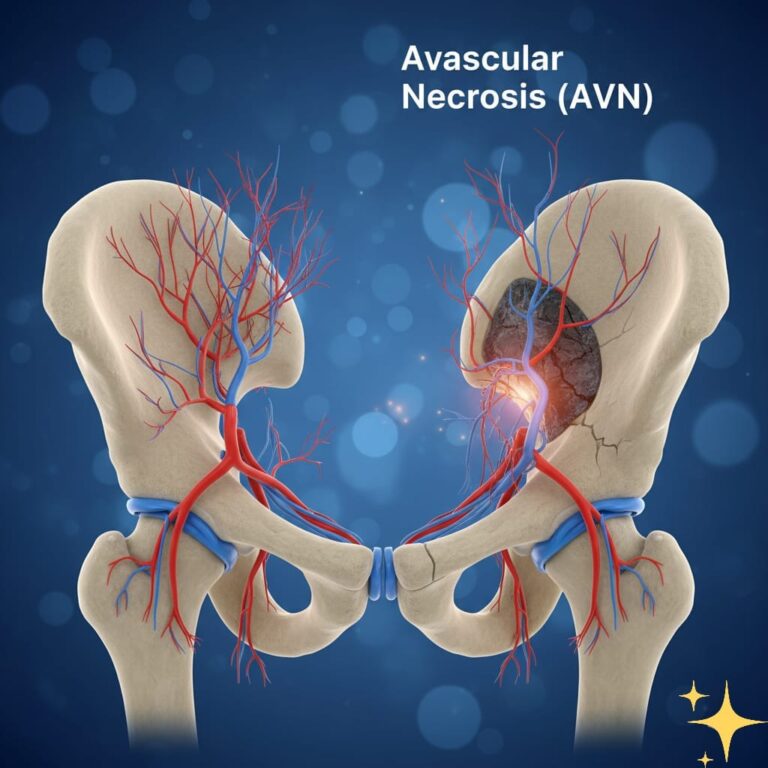

فهم المرض، أسبابه، أعراضه، طرق العلاج وأهم النصائح للوقاية والتعافي مقدمة: حقيقة العظام الحية يظن الكثيرون أن العظام مجرد دعائم صلبة في الجسم، لكن في الواقع هي أنسجة نابضة بالحياة تعتمد على تدفق دم مستمر لتبقى قوية وسليمة. عندما ينقطع…